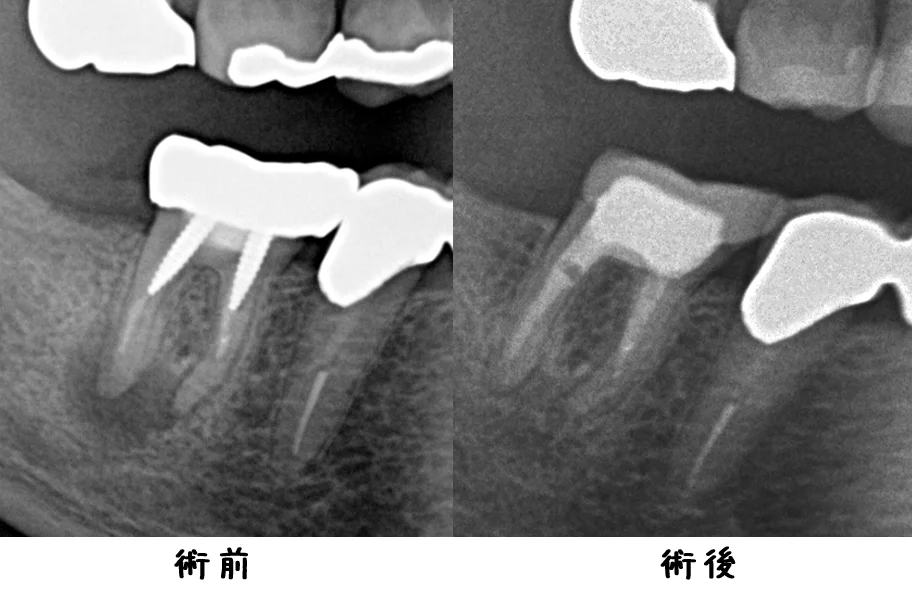

今回1年後の経過としてレントゲンを撮影させて頂いたのが、こちらです。

根の先の膿が完全に消えてくれたのが分かるかと思います。

入れたセラミックも適合良く入ってくれています。

治療を開始してからは痛みなどは一切出ずに、順調に過ごせているとのことでしたので、良かったです。

抜かないで済んでよかった~と喜んでいただき、幸いです。

ただ、予後が悪いことに変わりはありませんので、今後も定期的に診査させて頂くことになると思います。